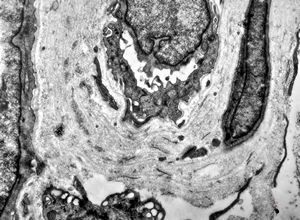

stabbed hypostom of the tick … toluidine-stained semithin section

stabbed hypostom of the tick … toluidine-stained semithin section (montage)